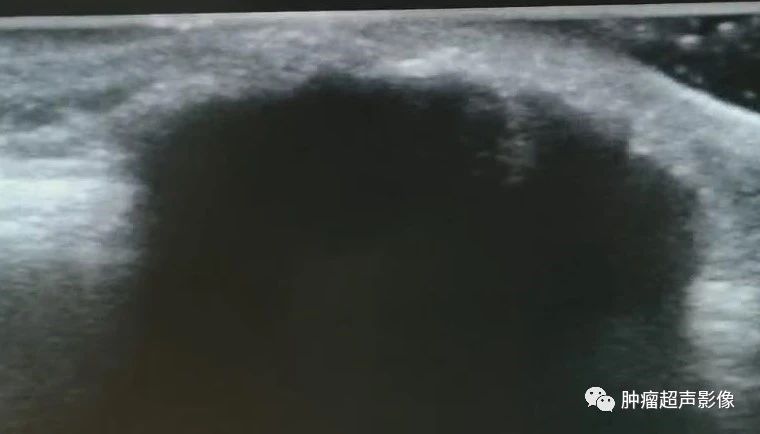

男35,颌下可移动无痛性肿块,皮肤真皮与皮下脂肪层交界处见低回声,边界清,内见血流,无钙化的容易误诊,除了无钙化,其它均符合毛母质瘤的特点。